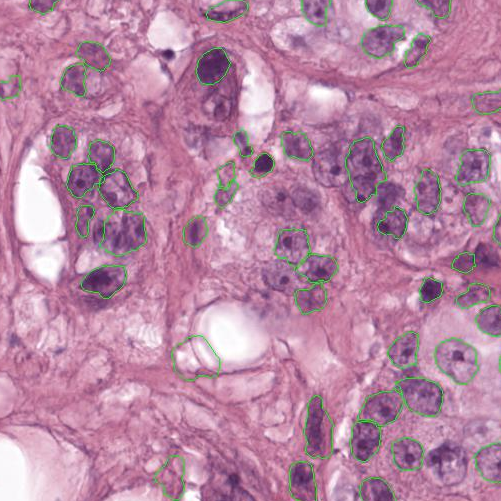

As an essential part of digital pathology, histopathology image analysis is playing increasingly important role in cancer diagnosis, which can provide direct and reliable evidence to diagnose the grade and type of cancer. This paper deals with nuclei segmentation, an important step in histopathological image analysis. The purpose of nuclei semgentation is not only counting the number of nuclei but also obtaining the detailed information of each nucleus. So unlike nuclei detection, here the outputs are the contour of each nucleus instead of only the position of their central points. Hence we can exactly extract each nucleus from the image and make it available for further analysis. For example, the features of the individual nucleus and the distribution of nuclei clusters can be used to grade and classify status of breast cancers [3, 4]. Because of appearance variation such as color, shape, and texture, nuclei segmentation from histopathological images could be very challenging, as illustrated in Fig.1, in which it is very challenging even for human to recognize and segment all nuclei within the images. Fig.1(a) and Fig.1(b) illustrate two histopathological images from different organs. Fig.1(c) and Fig.1(d) are two histopathological images from same organ but have different cancer grade.

H&E stain is the most widely used stain protocol in medical diagnosis. Typically, the nuclei of cells are stained to blue by Haematoxylin while cytoplasm is colored to pink by Eosin. But in practice, the color of H&E stained images could vary a lot due to variation in the H&E reagents, staining process, scanner and the specialist who performs the staining, as shown in Fig.1. A few H&E stain normalization methods[23, 24, 25] have been proposed to eliminate the negative interference caused by color variation. We tried two of them[23, 25] to normalize the raw H&E stained images. For our segmentation algorithm, we did not find any considerable difference between these two normalization methods. Particularly, the result shown in experiment section III is generated based on the images normalized by the method in [23]. Given a target image, this method is able to convert one image’s color into the target image’s color space based on sparse non-negative matrix factorization(NMF). We choose one best stained H&E image as the target and convert other images into its color space. According to the recommendation in [23], the hyper-parameter should be set between 0.01 and 0.1. In our experiment, is set to 0.1.